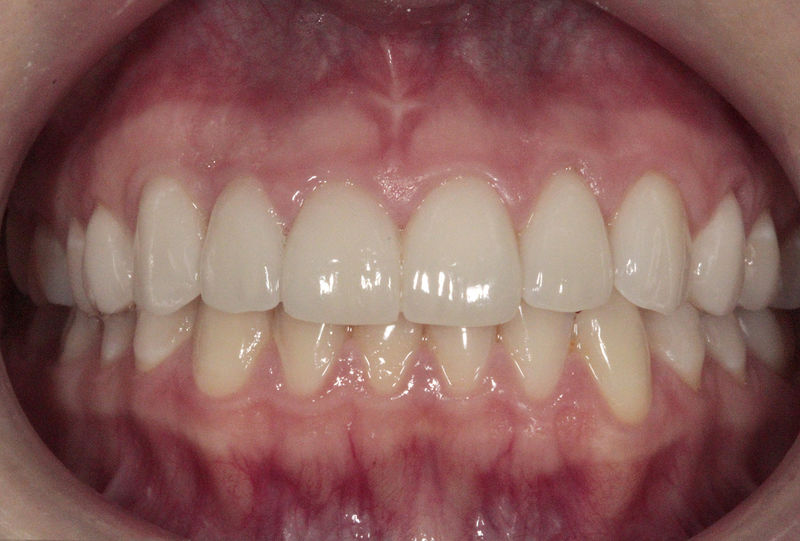

Ortodoncia y coronas.